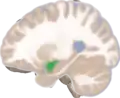

Location of the amygdalae in the human brain | |

Frontal and side view of amygdala

Frontal and side view of amygdala Amygdala along with other subcortical regions, in glass brain.

Amygdala along with other subcortical regions, in glass brain. Dorsal view of the amygdalae in an average human brain

Dorsal view of the amygdalae in an average human brain Frontal view of the amygdalae in an average human brain

Frontal view of the amygdalae in an average human brain Left lateral view of the amygdala in an average human brain

Left lateral view of the amygdala in an average human brain Amygdala highlighted in green on coronal T1 MRI images

Amygdala highlighted in green on coronal T1 MRI images Amygdala highlighted in green on sagittal T1 MRI images

Amygdala highlighted in green on sagittal T1 MRI images Amygdala highlighted in green on transversal T1 MRI images

Amygdala highlighted in green on transversal T1 MRI images